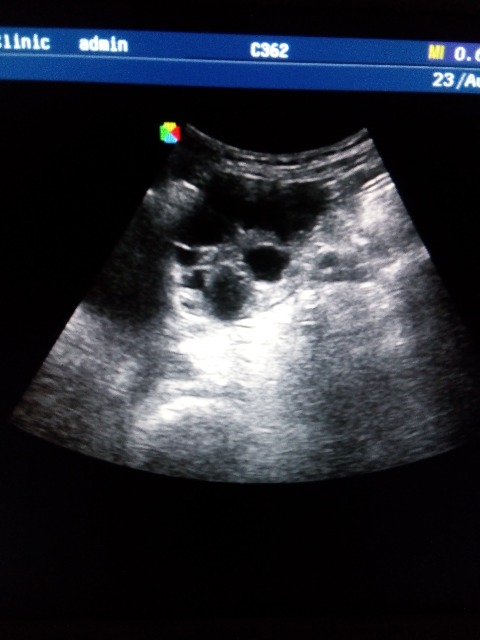

Подскажите что это может быть, лоцируется на уровне дна матки, справа и слева, больше слева, у женщины c-r шейки матки, проходит обследование брюшной полости перед лечением в онкодиспансере, недавно делали УЗИ малого таза, без патологии, никаких образований, кист не находили, жалоб нет. Думаю расширенные петли кишечника, заполненные жидким содержимым, перистальтики не увидела, если это они то какая может быть причина, и как то нужно это в протоколе и заключении отразить?

По фото можно подумать и про яичники и по некоторым фото про петли. Нужно видео!

Форма вытянутая, общей капсулы нет и с двух сторон, наверное кишечник, просто я его таким не видела еще.. ну а если абстрагироваться от этого случая, то что вообще писать в заключении в случае расширенных и заполненных жидкостью петель, если больной амбулаторный планово пришел? какие рекомендации?

Мария, побольше информации по пациентке - какое было лечение, и если получится видео, конечно.

еще может быть вот это - смотрим снимок 3 в статье